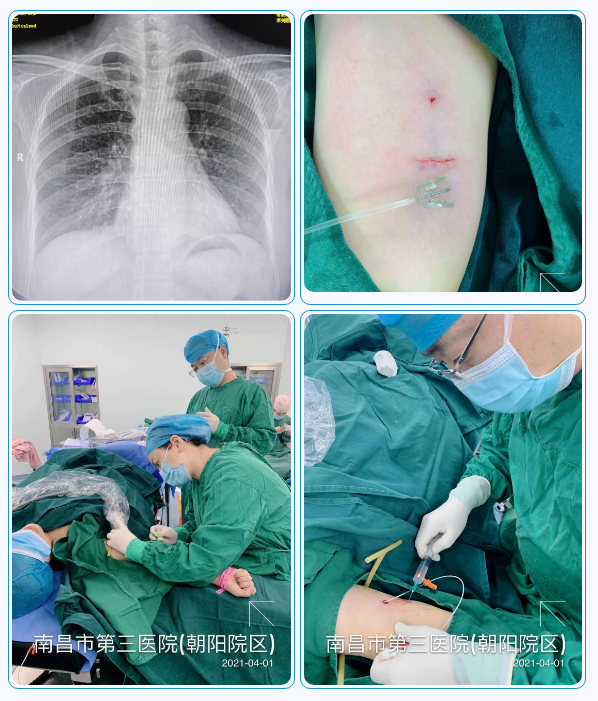

4月1日,捕鱼游戏 顺利完成首例手臂输液港植入术,标志着捕鱼游戏 静脉输液医疗护理水平又迈上新台阶,静脉治疗水平已达到江西省领先水平。

上午11时,在捕鱼游戏 乳腺中心主任曹亚丽教授的指导下,由乳腺一科副主任刘秋明和PICC门诊副护士长邓勤通过医护合作的形式,完成捕鱼游戏 首例手臂港植入术。手术顺利,整个操作过程20分钟,结合心电定位技术,为患者确定***的CAJ导管位置。

手臂港植入术为最新的静脉治疗技术,是在超声引导下置入上肢静脉导管,将输液港底座埋置于上臂内侧。目前,乳腺肿瘤患者接受化疗,一般选择PICC导管和胸壁输液港,而手臂输液港有更多优势,如下:

手臂输液港的顺利开展,为需要长期输液或化疗的患者带来了福音,大大提高了患者的生活质量,患者可以根据自己的情况,选择更加适合自己的静脉给药途径。我们将持续追踪,患者留置手臂输液港期间的感受和生活质量,为更多的病友提供更优质的服务。